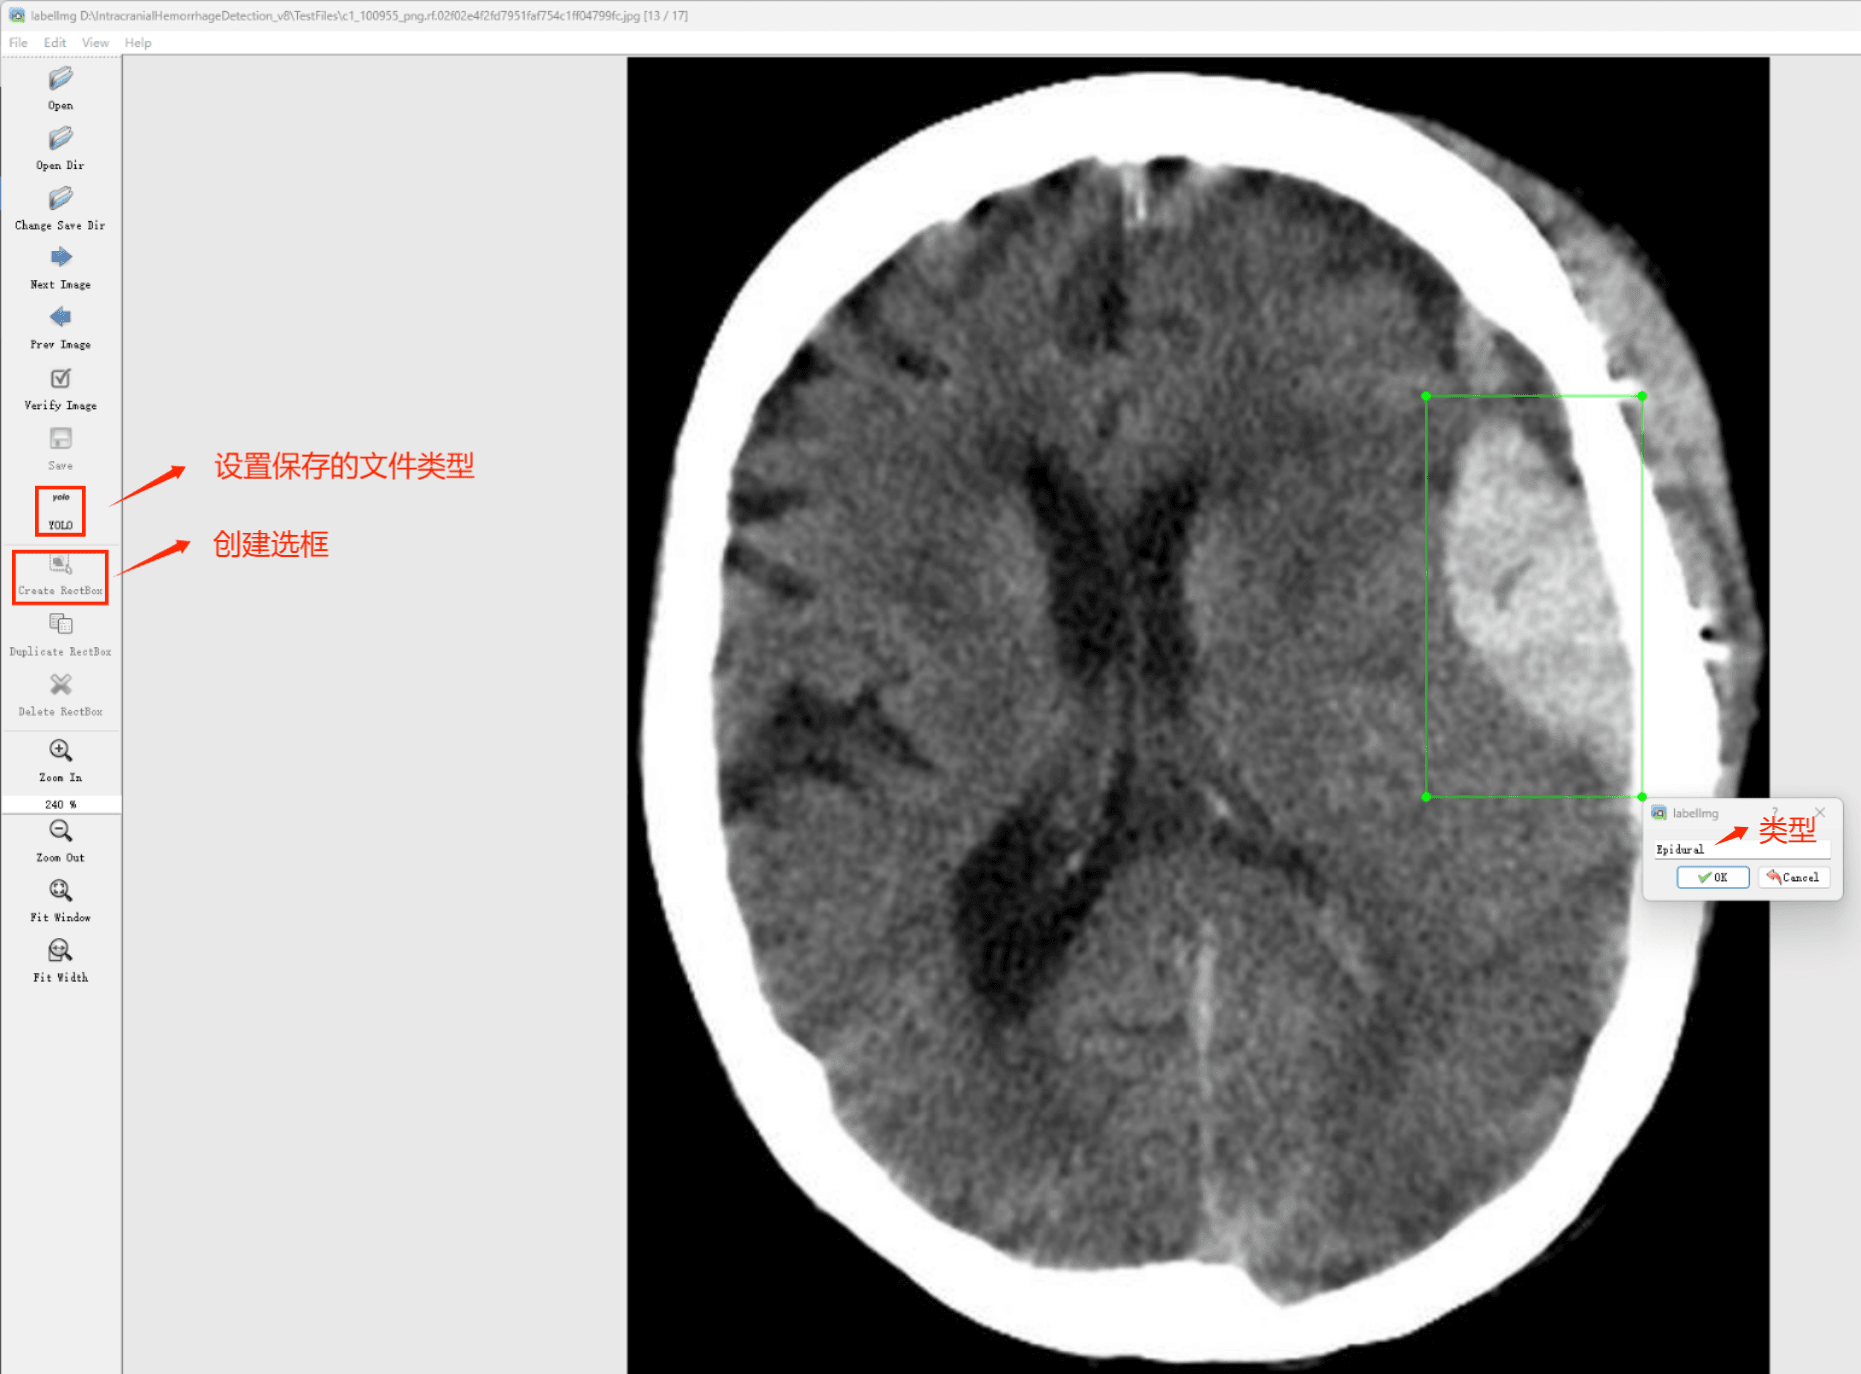

初识labelimg

打开后,我们自己设置一下

在View中勾选Auto Save mode

接下来我们打开需要标注的图片文件夹

指定标注文件存储的位置(如上图所示),开始执行标注流程。首先用矩形框选中目标区域,并对目标添加标签;随后切换至下一张图片继续操作。